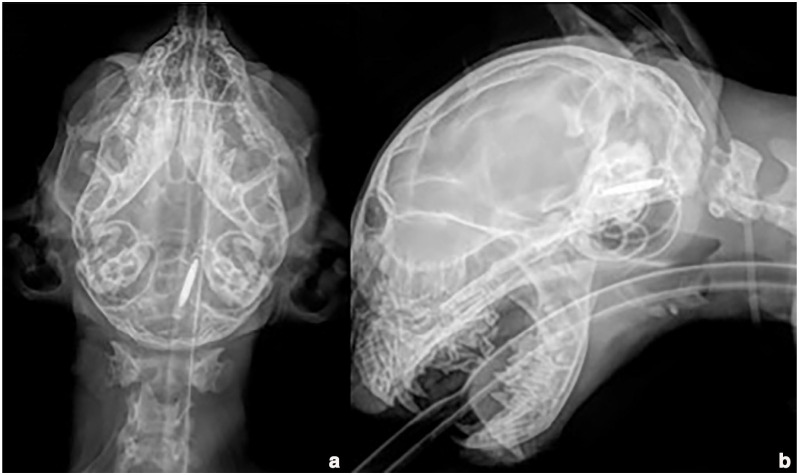

Case summary: A 2-month-old kitten was presented for ataxia and depressed mental status after implantation of a pet identification microchip. Radiographs were taken immediately by the referring veterinarian and showed a longitudinal metallic foreign body (electronic microchip) within the cervical vertebral canal at the craniocervical junction. A CT examination 2 days after the incident showed cranial migration of the microchip ventrally to the caudal brainstem. Ventral basioccipital craniectomy was immediately performed to retrieve the microchip by a ventral approach to the caudal brainstem. Postoperative recovery was uneventful and the cat was discharged 2 days later. At the 2-week follow-up, neurological examination of the cat was normal. No long-term complications were reported.

Relevance and novel information: This case report describes the intradural migration of a microchip and surgical removal via ventral basioccipital craniectomy.